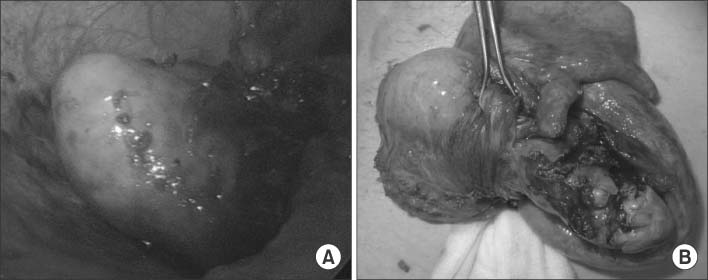

A contrast-enhanced abdominal CT scan revealed a 4.3×2.3 cm mass-like lesion beneath the cecum in the RLQ and an invisible normal appendix (Fig. 1).

Fig. 1

CT image shows a 4.3×2.3 cm mass-like lesion beneath the cecum within the right lower quadrant (arrow). This finding suggested differential diagnosis of advanced appendicitis with phlegmon or a tumorous condition.

Fig. 1 CT image shows a 4.3×2.3 cm mass-like lesion beneath the cecum within the right lower quadrant (arrow). This finding suggested differential diagnosis of advanced appendicitis with phlegmon or a tumorous condition.